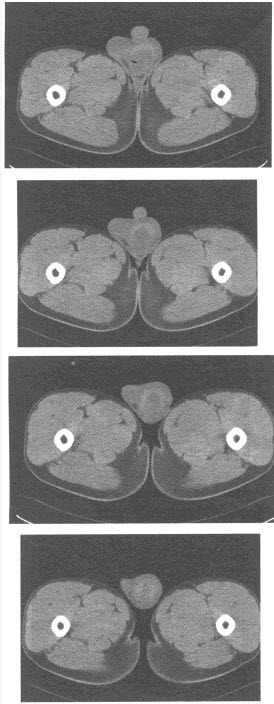

患者,男,73岁。入院诊断:急性阑尾炎并行急诊阑尾切除。术后腹痛症状不改善,不排气、不排便3天。行钡灌肠检查,如图。

(单选题)该患者最可能的诊断是()

E:乙状结肠扭转